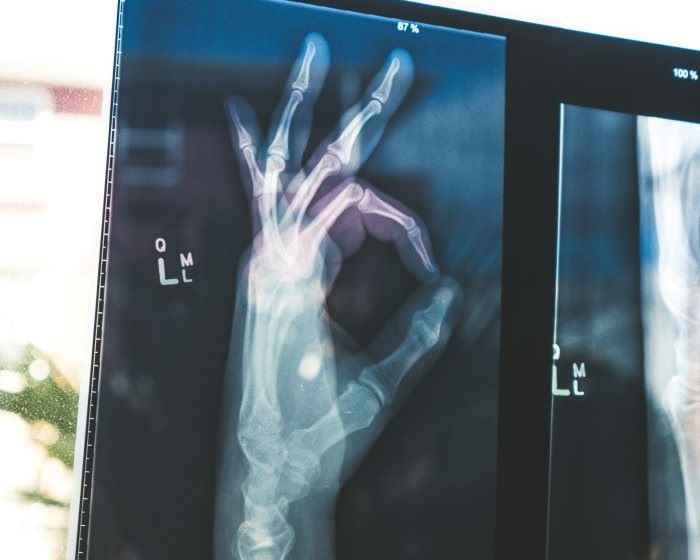

結論:レントゲンは「X線の通りやすさの違い」で体の中を映しています

X線は体を通り抜けます。

ただし、骨のように硬い部分は通りにくいです。

👉 この差が「白と黒の画像」として見える仕組みです。

X線で骨が見える理由

ここが一番大事です👇

X線は、すべて同じように通り抜けるわけではありません。

• 骨 → 硬くて密度が高い → 通りにくい(白く映る)

• 筋肉や脂肪 → 柔らかい → 通りやすい(黒っぽく映る)

• 空気(肺) → かなり通る → 黒く映る

👉 この違いで体の中が見えるんです。